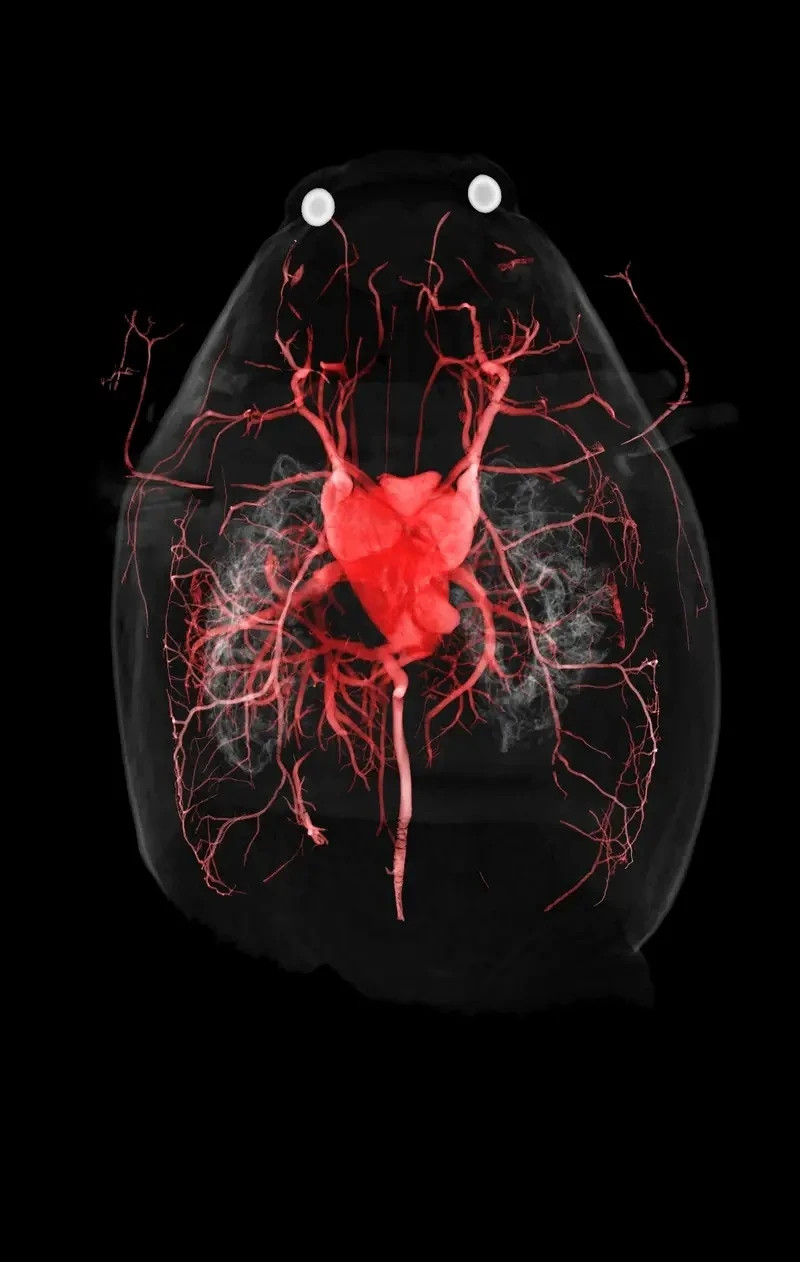

Ếch cừu: Điểm độc đáo của theo dõi này là hệ thống mạch máu của ếch cừu phương bắc, với điểm nhấn là trái tim chiếm phần lớn diện tích cơ thể nó.